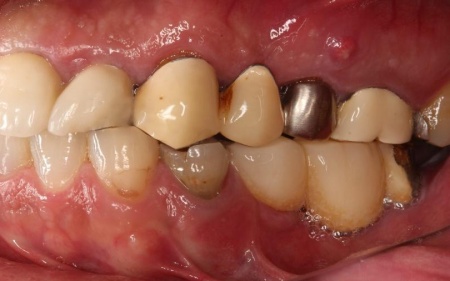

治療前

また、右上前歯も1本欠損しており、両隣の歯を土台として橋を渡すように連結した被せ物「ブリッジ」が装着されていましたが、土台となっている右上前歯2本(中切歯、犬歯)が割れており、温存が難しい状態です。

さらに、劣化してうまく適合していない被せ物、詰め物、既存のインプラントが複数見られ、これらも噛み合わせを乱す原因となっていました。

加えて全体的に歯周病も進行しており、骨が溶けている部分も確認できます。

このまま放置すると、食事がしにくい、残っている歯への負担が増えて歯の寿命が短くなるなどのリスクがあるため、早急に治療を開始する必要があると診断しました。